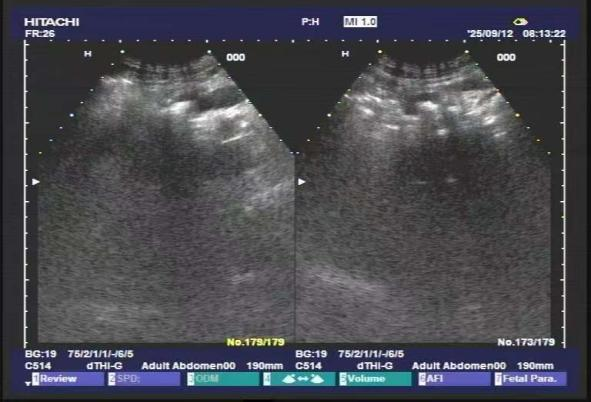

左图:碎石前 右图:碎石后

术后